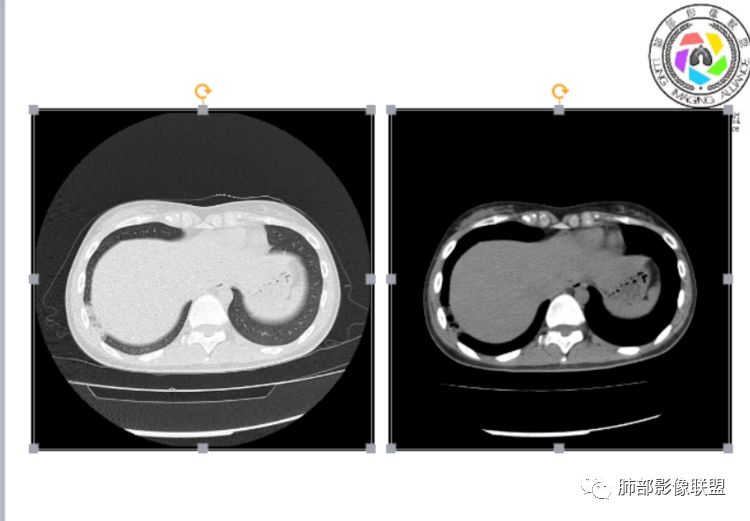

小微:右肺下叶斑片状密度增高影,抗炎治疗6天后复查,双肺下叶出现斑片状密度增高影,排除炎性病变,D2聚体特别高,考虑肺栓塞,肺梗死,建议增强扫描。王开金江津中心医院呼吸科:@岳微-辽宁PLA234医院放射科?支持,患者年轻女性,胸痛主诉,使用雌激素,高危人群,心率快,d二聚体升高,右下叶斑片加肺动脉明显增宽,抗感染无效,要考虑PTE,建议肺动脉ctpa。傅昌瑜:19岁,女性,右侧胸痛2天,发热以中度热为主,D—二聚体升高,肺动脉主干增宽,病灶位于胸膜下,抗感染后增多,近来有服用炔雌醇环丙孕酮片2周期史,诊断:肺栓塞,下一步完善肺CTPA检查。阿仙奴:青年女性,急性起病,胸痛入院,月经不调史,目前服用孕酮片。流感抗体阳性,d二聚体升高,无低氧血症。右肺下叶基底段胸膜下磨玻璃样改变,肺动脉增宽,治疗过程出现发热,复查左下叶胸膜下新发病灶。考虑:肺栓塞(服用孕酮相关)?奔跑的37°Doctor(陆喜红 ) :年轻女性,胸痛 急性病程,有服用雌激素避孕药史(是否有血液循环的改变,高凝状态),实验室D二聚体很高(也是提示血液高凝状态) ,第一次CT,右下肺胸膜下斑片状密度增高模糊影,肺动脉形态密度未见明显异常,抗炎后复查,肺动脉干及其分支,感觉增粗了一点,局部形态有点饱满,双下肺胸膜下片状影增多,锁定肺动脉栓塞应该不会错,建议CTA检查飞鹰行动:青年人,女性,右肺下叶斑片状密度增高影,抗炎治疗6天后复查无好转,,双肺下叶出现斑片磨玻璃影,主肺动脉增粗,结合患者服用的药物和D2聚体特别高,考虑肺栓塞,建议CTA。李:口服避孕药,有危险因素,肺动脉较主动脉增宽,D二聚体增高,胸膜下片状影,考虑肺栓塞;@晨义工张帅,医附属潞河医院呼吸?是否痰中带血很关键,不知有没有张帅:患者入院后第七天出现痰中带血风之子:病程中有发热,D—二聚体升高,肺动脉主干增宽,病灶分布于胸膜下,抗感染后增多,结合服药史诊断:肺栓塞,建议CTPA检查。不支持的地方是没有低氧血症,不明白为什么第二次复查ct双侧乳腺不对称,按理乳腺炎多见于哺乳期张帅:大家方向都在考虑肺栓塞:我提问两个问题:1 周围毛玻璃怎么回事?2左下肺小叶间隔增宽怎么回事?笨丫头:周围的磨玻璃应该考虑是肺梗死后出血渗出,同时合并机化性炎症小叶间隔增宽,我考虑应该是梗死后炎性渗出wonderful:我不支持肺栓塞 不能解释发热原因

笨丫头:肺栓塞也会发热呀王江涛:肺内子宫内膜异位症,合并梗死出血Lenle董:外围渗出性改变,出血?左下肺的支气管镜不会看张帅:呼吸困难比较难判断,尤其对于一个有胸痛的患者来说@唐大川新沂市人民医院呼吸科风之子:对,要警惕子宫内膜异位症岁月:病史:女,19岁;右侧胸痛2天;血常规17.4,中性粒75.7%,右下肺斑片影;月经不调,雌激素?治疗;D2高,3974.78,支气管镜阴性。治疗方式,抗炎。病史诊断方向:肺栓塞?影像:首先找肺栓塞影像。6天后CT可疑肺栓塞;作者量肺动脉23.7mm,提示什么?好像和同层面主动脉宽度相当,先心病?肺血无明显改变?双肺斑片影,左侧磨玻璃,边界清楚,还有些散在不清楚,左侧为甚,胸膜下贴,三角形?左侧少了胸水;诊断:肺栓塞;鉴别:先心合并肺栓塞?肺炎。

张帅:我量的虽然不标准,但不到24

CT平扫及间接征象:

1、一个或多个胸膜下斑片高密度影(梗死、出血、肺不张、肺水肿、炎性渗出),典型为胸膜下楔形影 ,尖端指向肺门

2、肺动脉高压(中心肺动脉扩张),有时可见肺动脉区高密度影。

3、肺血减少

4、马赛克灌注

5、膈肌升高、胸腔积液、心包积液

3.影像:病变胸膜下多发斑片影,提示与血管有关,早期病变为渗出,应该是早期的炎性渗出,病灶抗感染治疗后实变区增多、变大,临床症状又出现咯血,CT上应该合并了肺泡出血、梗死、肺不张及肺水肿;